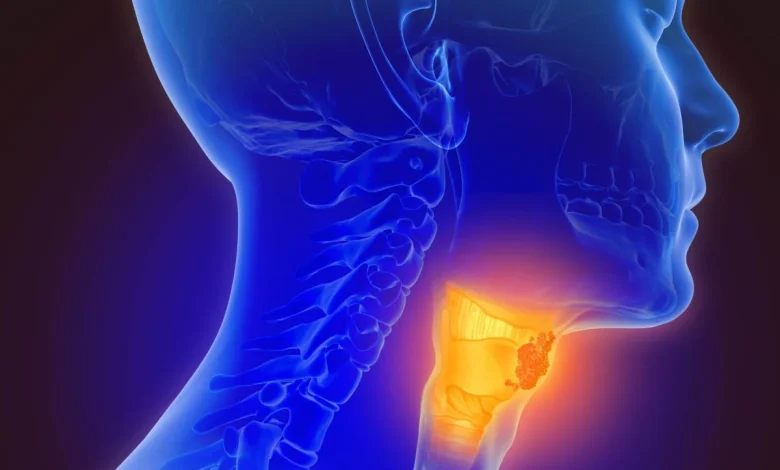

ووفقًا لمختصين، فإن التهاب الغدد اللمفاوية يحدث عادة بسبب عدوى بكتيرية أو فيروسية، ويظهر التورم بشكل سريع، ويكون مؤلمًا ومصحوبًا بأعراض مثل الحمى أو التهاب الحلق، كما يتراجع تدريجيًا خلال أيام أو أسابيع مع العلاج.

في المقابل، يظهر سرطان الغدد اللمفاوية نتيجة نمو غير طبيعي للخلايا، ويتطور التورم ببطء، ويكون غالبًا غير مؤلم وصلب وثابت في مكانه. وقد ترافقه أعراض عامة مثل فقدان الوزن بدون سبب، التعرّق الليلي، وفقدان الشهية.

ويؤكد الأطباء إمكانية التمييز بين الحالتين عبر الفحص السريري وتحاليل الدم وأشعة الموجات فوق الصوتية، بينما تُعد الخزعة الوسيلة الأكثر دقة للكشف عن السرطان عند استمرار التورم أو عدم وجود سبب واضح له.

ويختلف العلاج تبعًا للحالة؛ فبينما تعالج الالتهابات بالمضادات الحيوية أو الأدوية المضادة للفيروسات، تحتاج الحالات السرطانية إلى علاجات متخصصة مثل العلاج الكيماوي والإشعاعي أو المناعي.

وينصح الأطباء بضرورة استشارة الطبيب عند استمرار التورم لأكثر من أسبوعين، أو ظهور أعراض مقلقة دون تفسير، مؤكدين أن التشخيص المبكر يسهم في نجاح العلاج وتجنب المضاعفات.